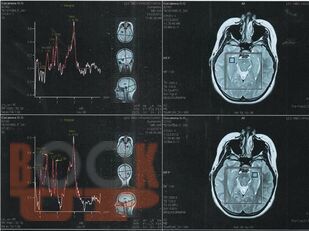

В учебном пособии освещены современные подходы к патогенезу височной эпилепсии, связанные с процессами нейровоспаления и нейродегенерации. Отражена углубленная информация о клинико-диагностических маркерах заболевания, в том числе, касающаяся изучения биохимических и генетических биомаркеров височной эпилепсии.